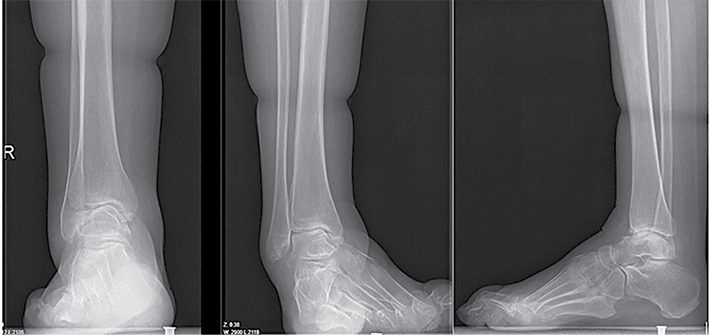

Antruoju atveju 38 m. pacientė kreipėsi į LSMU KK dėl deformuotų pėdų. Deformacijos prasidėjo vaikystėje. Dėl deformacijų sunku eiti, krypsta kojos, sunku pritaikyti tinkamą avalynę. Tais pačiais metais diagnozuota CMT liga. Objektyviai matyti abiejų pėdų varus deformacija, subtalarinių sąnarių nestabilumo požymiai. Vertinant objektyviai: pėdos plantarinė fleksija ‒ 25°, dorsifleksija ‒ 5°. Prieš 20 m. atlikta abiejų pėdų I tarsometatarsalinių (TMT) sąnarių artrodezės, susiformavusi kaulinė ankilozė. Rentgenogramoje matyti abiejų čiurnos sąnarių I stadijos artrozė, varus tipo pėdų deformacija, aukštas pėdos skliautas. Pacientei taikytas konservatyvus gydymas buvo neefektyvus. Skausmo nejaučiama. Pagal EFAS čiurnos ir pėdos funkcijos vertinimas siekė 18 balų, pagal AOFAS – 62 balus. Siekiant sustabdyti pėdos deformacijų progresavimą, atlikta kairiojo kulnakaulio ašį koreguojanti osteotomija ir subtalarinio sąnario artrodezė dviem sraigtais, Hoke metodika pailginta Achilo sausgyslė, atlikta lateralinių čiurnos sąnario raiščių plastika naudojant inkaruojantį sraigtą, I padikaulio uždaro kampo kylinė osteotomija bei osteosintezė L formos 5 skylių plokštele ir 4 rakinamais sraigtais. Po operacijos rekomenduota 2 savaites laikyti koją pakeltą, imobilizuoti įtvaru 10 savaičių, neminti kojos 8 savaites, o vėliau palaipsniui didinti atraminį krūvį. Po 4 savaičių, išėmus koją iš įtvaro, mankštinti ją per čiurnos sąnarį ‒ čiurną lenkti ir tiesti, vengti sukti pėdą į šonus. Po 6 savaičių paskirta atvykti ortopedo-traumatologo kontrolinės konsultacijos. Reabilitaciją numatyta pradėti po 10 savaičių. Po metų rentgenologinėse nuotraukose matyti gera konstrukcijų padėtis, sugijusios osteotomijų zonos ir susiformavusi kaulinė ankilozė. Pagal EFAS ‒ 23, pagal AOFAS – 82 balai. Vertinant objektyviai: pėdos plantarinė fleksija ‒ 35°, dorsifleksija ‒ 10°.

5 pav. Kairės ir dešinės čiurnos bei pėdos rentgenogramos prieš operacijas